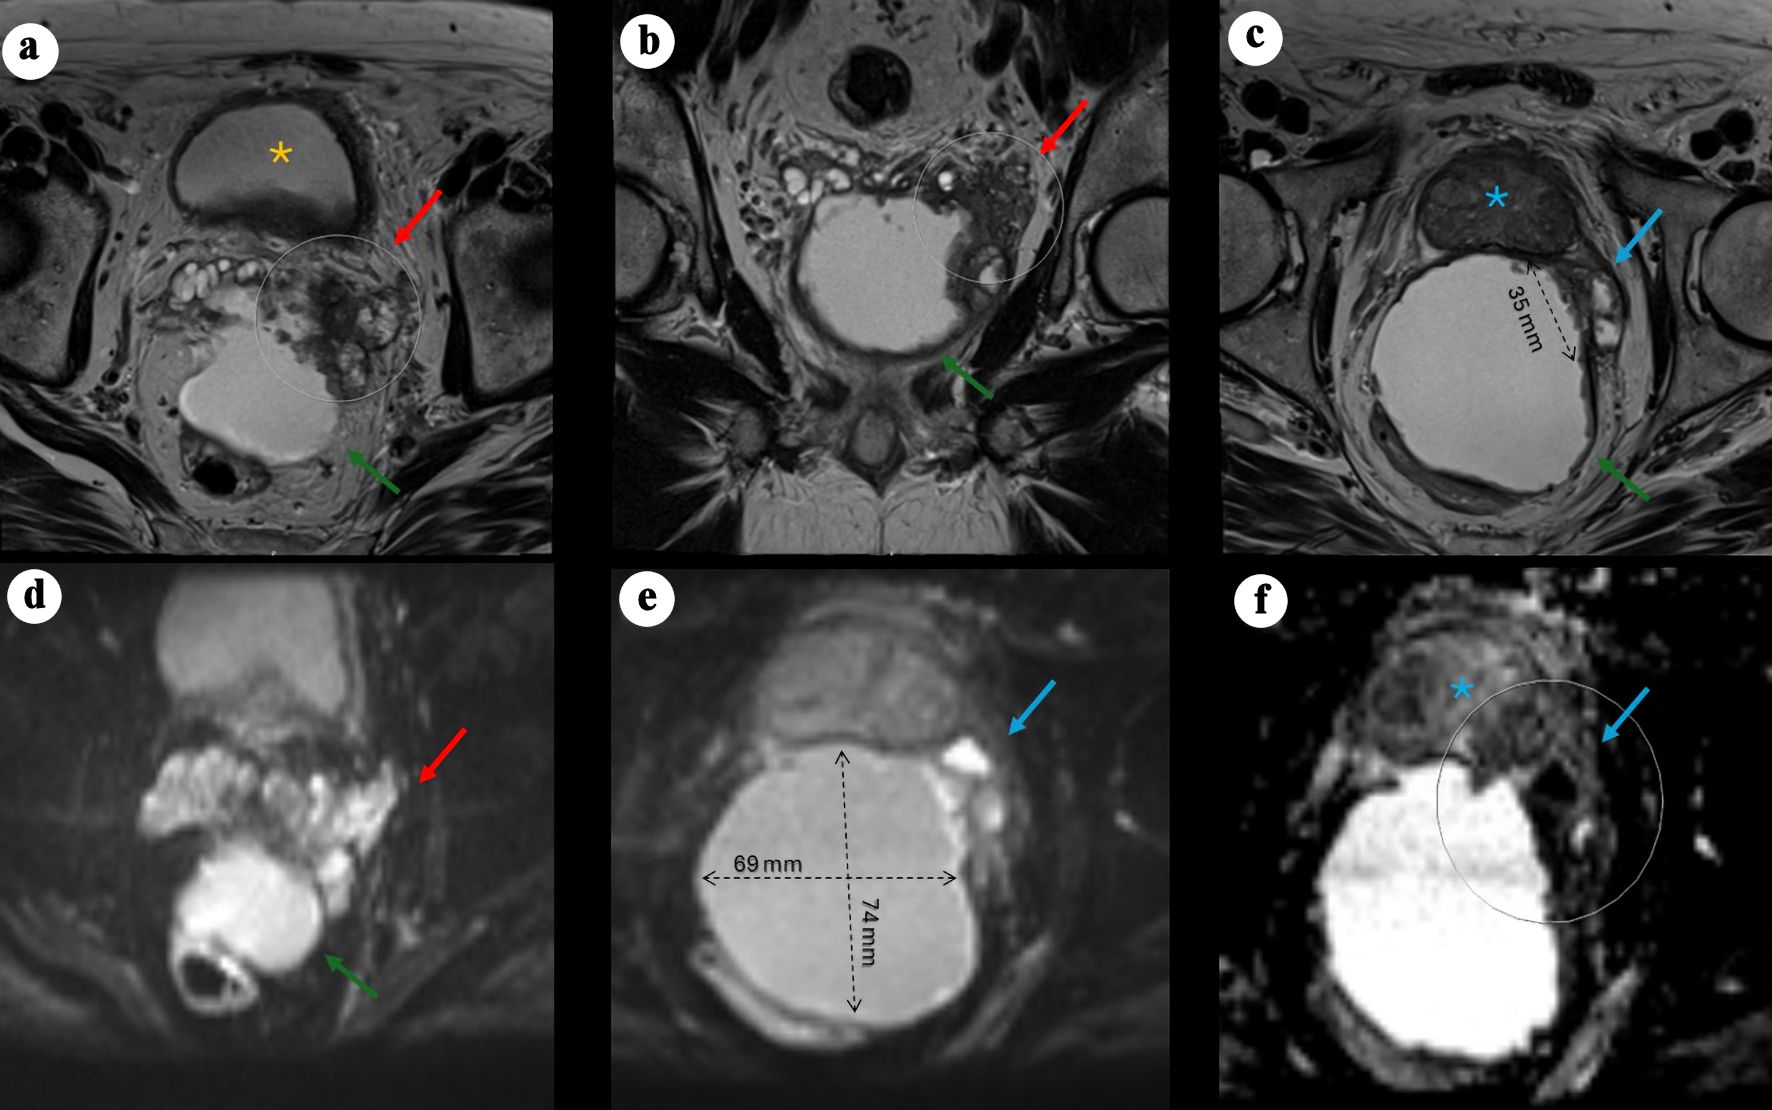

In April 2024, repeat pelvic MRI (Fig. 1) revealed a large (7.4 × 6.8 × 6.7 cm) predominantly cystic mass between the rectum and the posterior peripheral zone, with peripheral rim enhancement and diffusion-restricting nodularity. An additional smaller cystic focus (3.6 × 1.4 cm) was seen between the left posterior lateral mid-gland and the main lesion. Irregular T2-hypointense tissue extended between the left inferior SV, the cystic mass, and the left posterior lateral base of the prostate, suspicious for malignancy (PI-RADS 5) with extra prostatic extension. The transition zone was mildly enlarged without suspicious lesions. No abnormal pelvic lymph nodes or bone lesions were identified, and sigmoid diverticulosis was incidentally noted.

Figure 1. Pelvic MRI demonstrating a large cystic pelvic mass with features suggestive of malignancy. (a) Axial T2-weighted image showing a large, predominantly cystic mass (green arrow) situated between the rectum and the posterior left peripheral zone of the bladder (yellow asterisk), associated with a severely distorted left SV (red arrow) demonstrating hypoattenuation, suspected to originate from a left SV mass, with rim enhancement and peripheral nodularity (arrow). (b) Coronal view showing the mass located posteriorly and extending caudally. (c) Axial view demonstrating an additional smaller cystic focus (3.6 × 1.4 cm) between the left posterolateral mid-gland and the main lesion. Irregular T2-hypointense tissue extends between the left inferior SV, the cystic mass, and the left posterolateral base of the prostate, suspicious for malignancy (PI-RADS 5) with extraprostatic extension. (d) Axial DWI view of the mass. (e) Axial DWI showing marked diffusion restriction within the prostatic lesion and along the cyst lining (69 × 74 mm process). (f) Axial apparent diffusion coefficient (ADC) map demonstrating corresponding low signal. MRI: magnetic resonance imaging; PI-RADS: Prostate Imaging–Reporting and Data System; SV: seminal vesicle; DWI: diffusion-weighted imaging.